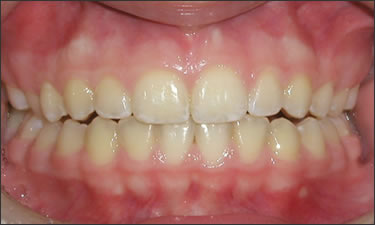

This patient experienced many areas of gum recession, primarily on the upper and lower front teeth. This patient's own tissue was used to correct the problem.

Click on a thumbnail to view the before and after photos.